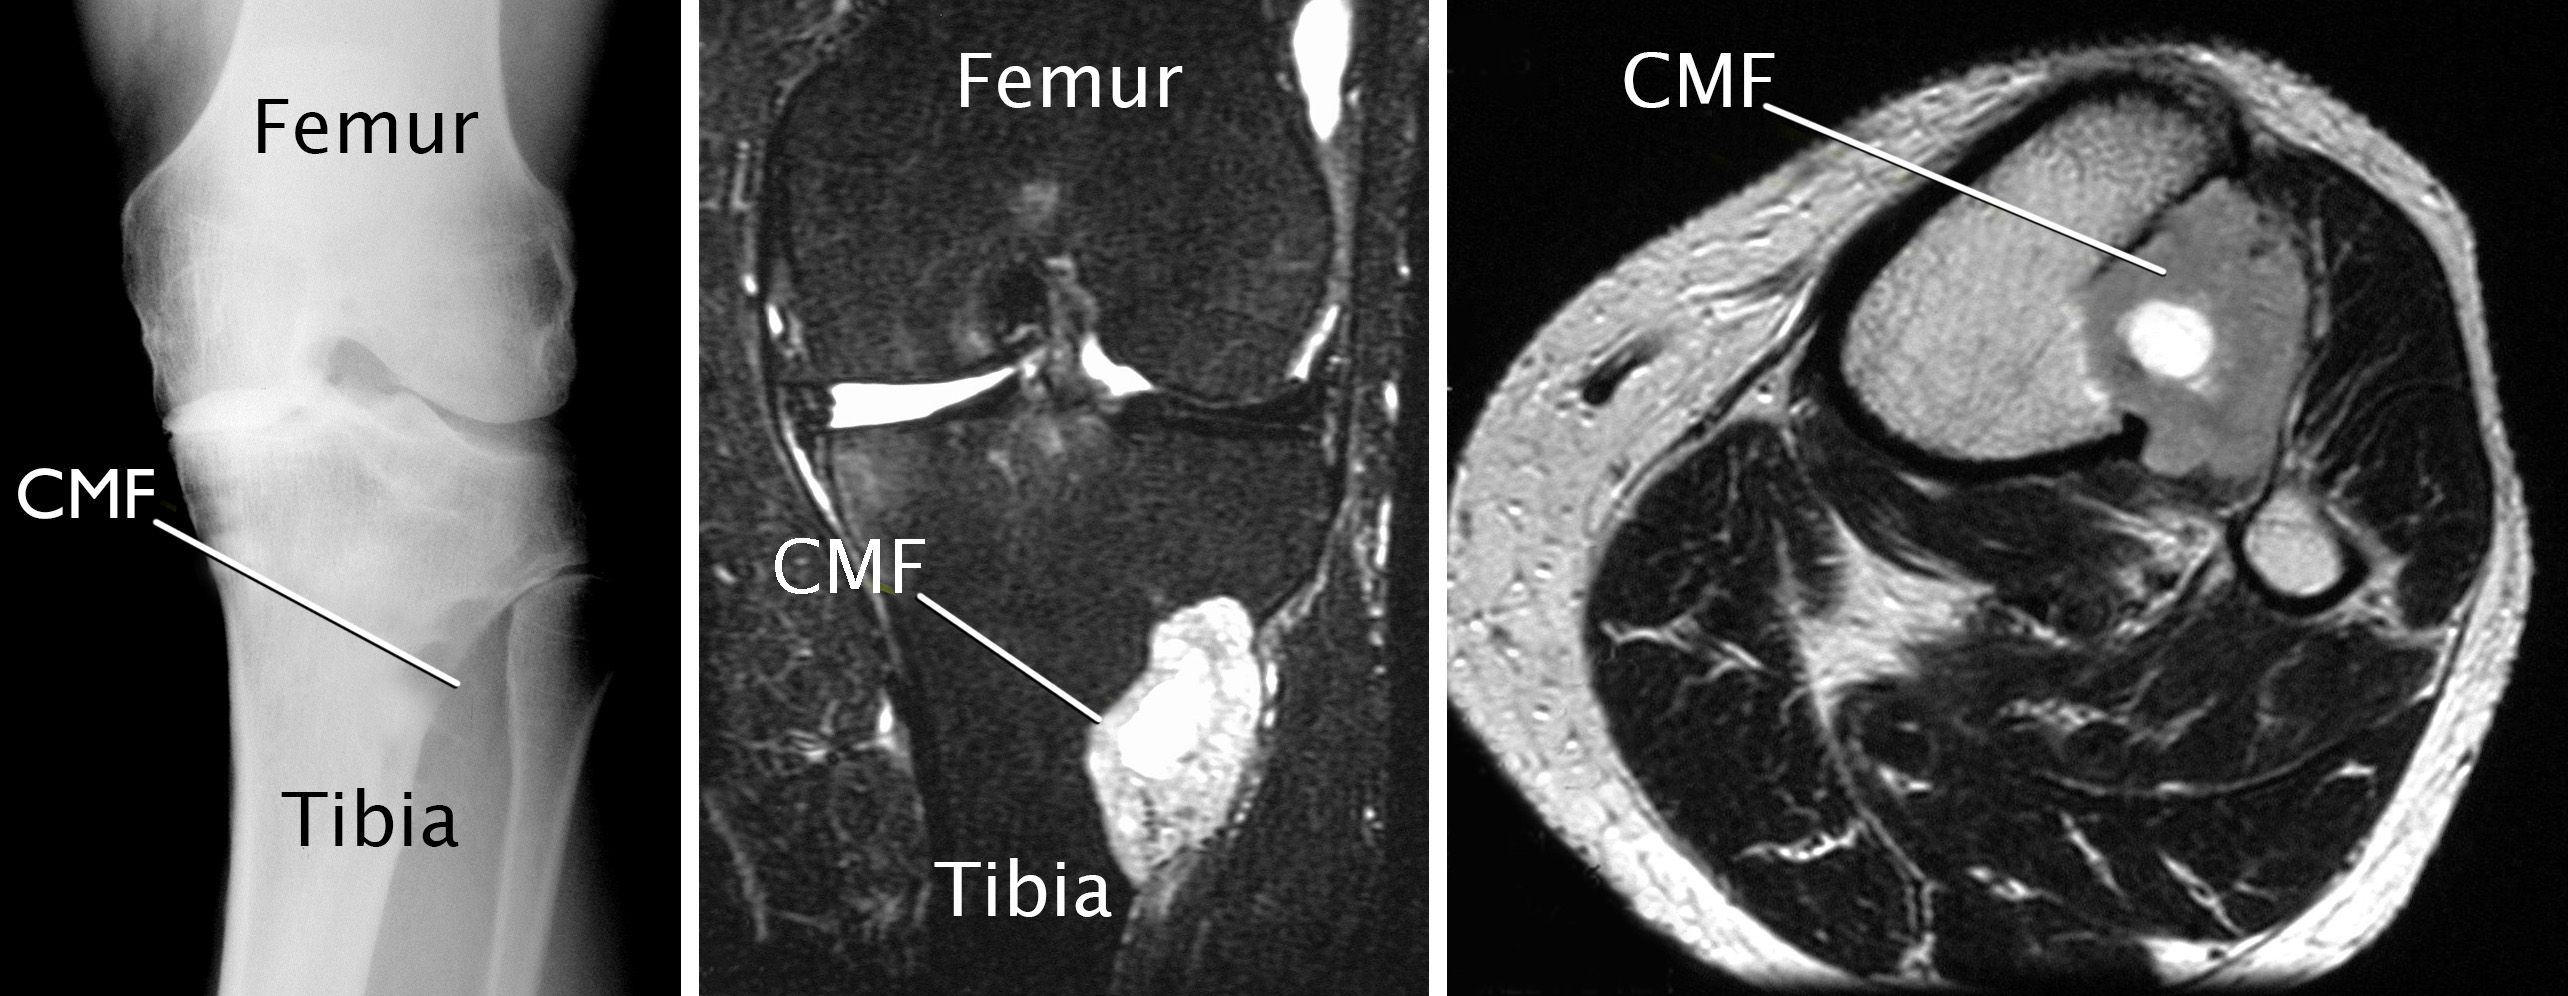

Other imaging tests. While there are usual features of CMF seen on X-rays, many other tumors can have a similar appearance. That is why doctors usually also request computed tomography (CT) scans or magnetic resonance imaging (MRI) scans to help confirm the diagnosis and get a better idea of how much bone is affected by the tumor.

CT and MRI scans provide a lot of detail, especially of the soft tissues. They can also provide cross-sectional images (see image below, on the right) that allow your doctor to look at your tumor as though they sliced through it (along with the affected bone and muscle).

imaging scans of chondromyxoid fibroma

(Left) An X-ray image of a CMF located at the top end of the tibia. (Center) An MRI image of the same tumor. (Right) A cross-sectional MRI image of the same tumor. Note how the tumor has grown beyond the bone.